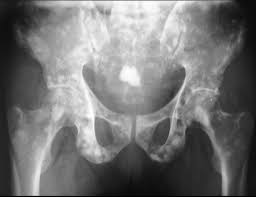

Bone Metastases Radiology Key

Bone Metastases Radiology Key from radiologykey.com